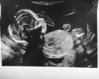

Augustjentenes UL bilder<3

Litt treig, da UL var 30.03, men har ikke oppdaget tråden før nå, hehe :) Fine lillemor <3